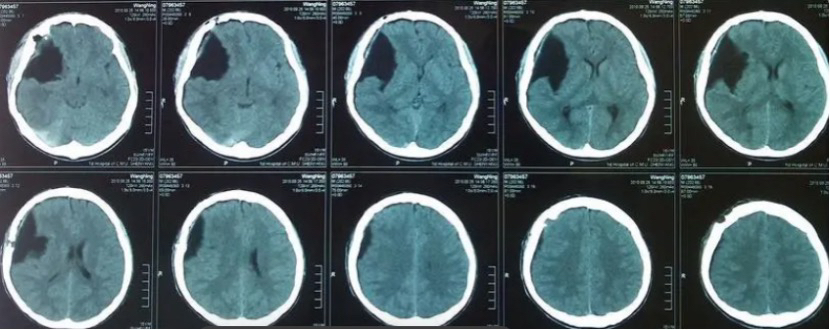

颅中窝囊肿可导致偏瘫蛛网膜囊肿的诊断常规应用CT和MRI检查一般可以确诊,仅在少数情况下针对中线部位鞍上和后颅凹病变,应用脑脊液对比剂或流量测定检查。1)CT:表现为边界光滑、无钙化的脑实质外囊性肿物,密度类似脑脊液。静脉注射对比剂无强化。2) MRI:在鉴别蛛网膜囊肿内容物与肿瘤囊液方面优于CT,并可显示囊种壁。

CT